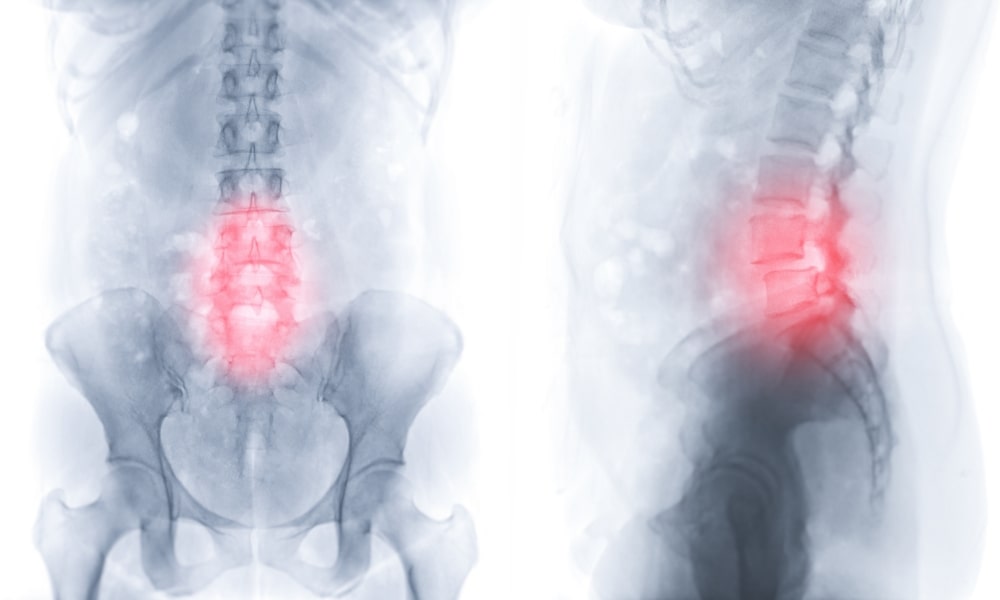

特異的腰痛(構造的または病的なもの)

腰痛の中でも、病院の画像診断や専門医の診察で「この異常が原因だ」と説明できるものがあります。代表的なものは以下のようなものがあります。

- 椎間板ヘルニア

椎間板の内部のゼリー状の組織が飛び出て神経を圧迫することで、腰だけでなく下肢の痛み・しびれ(坐骨神経痛)を伴うことがあります。 - 脊柱管狭窄症

脊柱管(脊髄・神経が通るトンネル状の空間)が狭くなり、神経が圧迫される状態。主に中高年以降で認められ、間欠性跛行(歩くと痛み・しびれが出て、休むと楽になる)が典型です。 - 変形性腰椎症(加齢性変化)

椎間板の変性や椎体の骨の変形が進行して、関節の不整、骨棘形成(骨がとげのように出ること)などが起こるもの。 - 腰椎分離症・すべり症